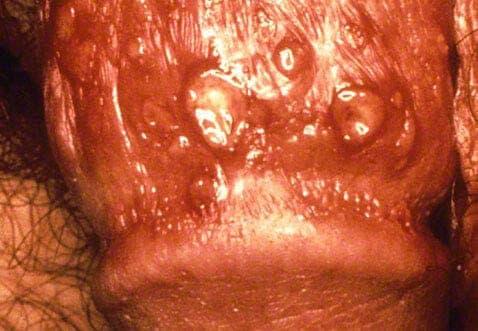

Os sintomas do herpes genital podem desenvolver-se rapidamente com bolhas vermelhas (lesões) desconfortáveis e por vezes dolorosas e úlceras de pele que se formam na zona genital, nas coxas, no ânus e no recto. O vírus permanece num nervo próximo, pelo que os surtos recorrentes ocorrerão sempre no mesmo local.

Após algumas horas de sintomas de pródromo, desenvolvem-se as feridas de herpes. Estas bolhas cheias de fluido têm comichão e também podem ser dolorosas quando rebentam, deixando feridas abertas que se irritam facilmente. Também pode sentir dor ao urinar ou corrimento vaginal anormal durante os sintomas activos.

Uma vez que as bolhas se exsudam, secam e ficam com crosta após alguns dias, mas para algumas bolhas podem demorar 2 - 4 semanas a cicatrizar. Podem rachar e sangrar nesta fase antes de as feridas terem cicatrizado completamente.

Note por favor: as imagens abaixo são explícitas por natureza.